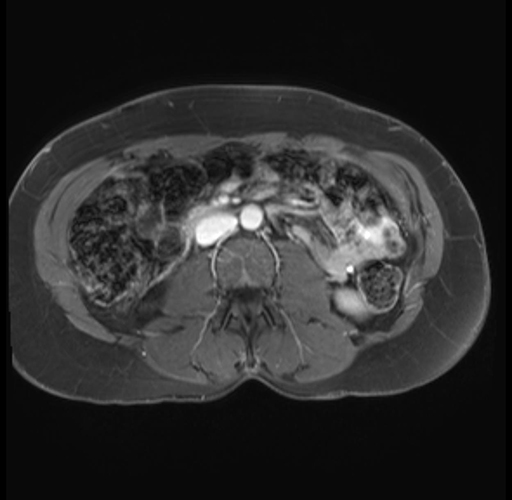

Imaging Analysis

Look through the patient's CT scan to identify any areas of concern for the necessary procedure.

Based on your CT findings, which issue(s) are present and would give reason for "planned slowing down moment(s)" in this case?